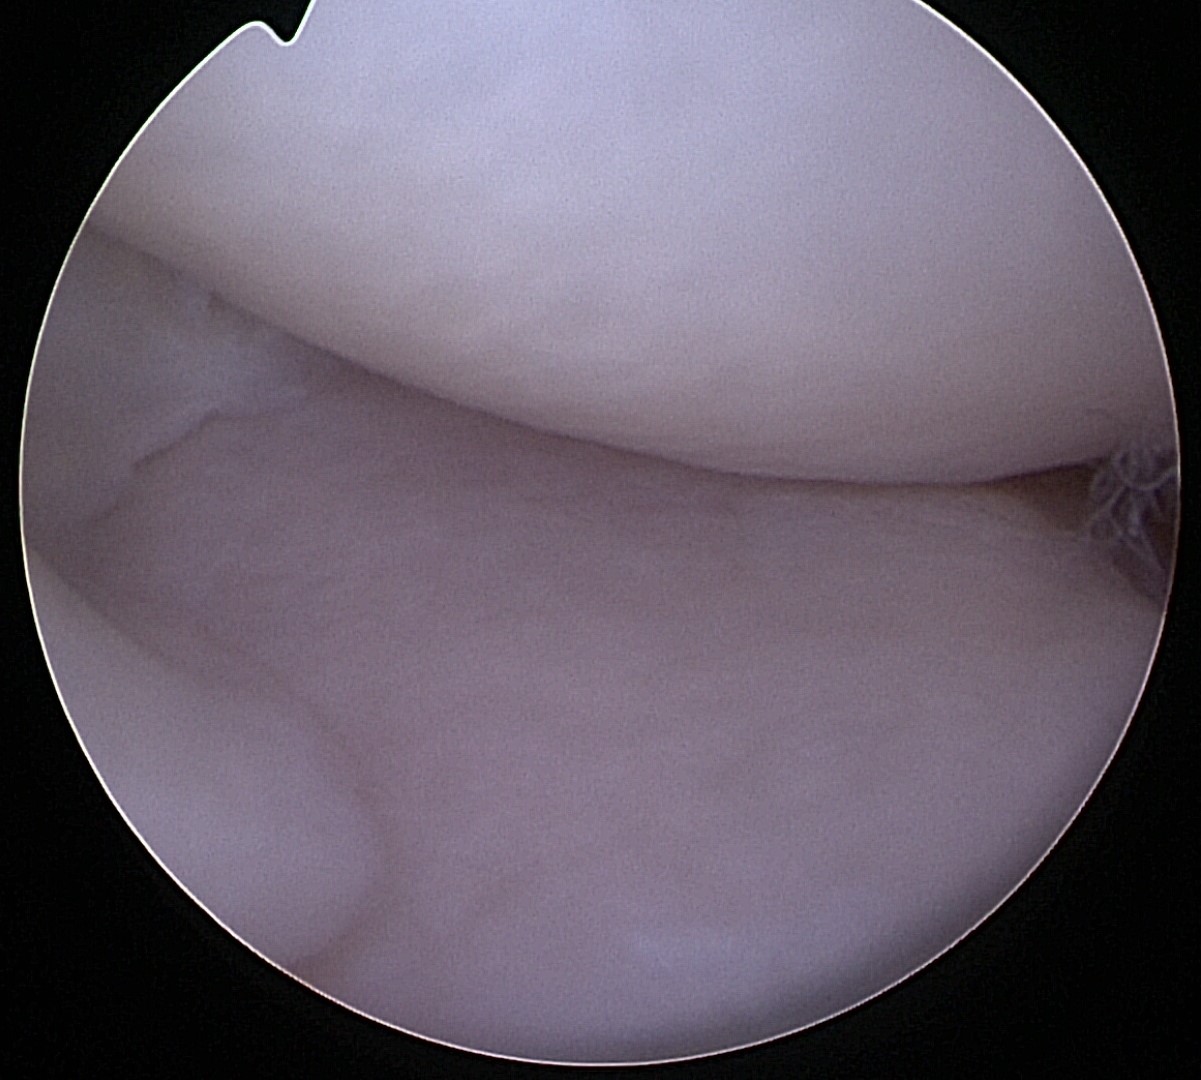

The following images and video demonstrate a normal canine medial meniscus.

There are two menisci (the medial meniscus and the lateral meniscus) in each dog knee that serves as cartilage cushions or shock absorbers.

Due to this shock absorbing effect, a healthy canine meniscus helps prevent the dog’s knee joint from wear and tear. In dogs with CCL injuries, the medial meniscus is often affected, while the lateral meniscus is rarely torn. Proper treatment of dog meniscus injuries following a CCL rupture includes thoroughly evaluating the menisci to ensure there is no tear.

Arthroscopy is one of the best methods to assess dog knee injuries, offering a minimally invasive and accurate way to detect tears. If a canine meniscus tear is found during the arthroscopy, the damaged portion is removed or, in rare cases, repaired.